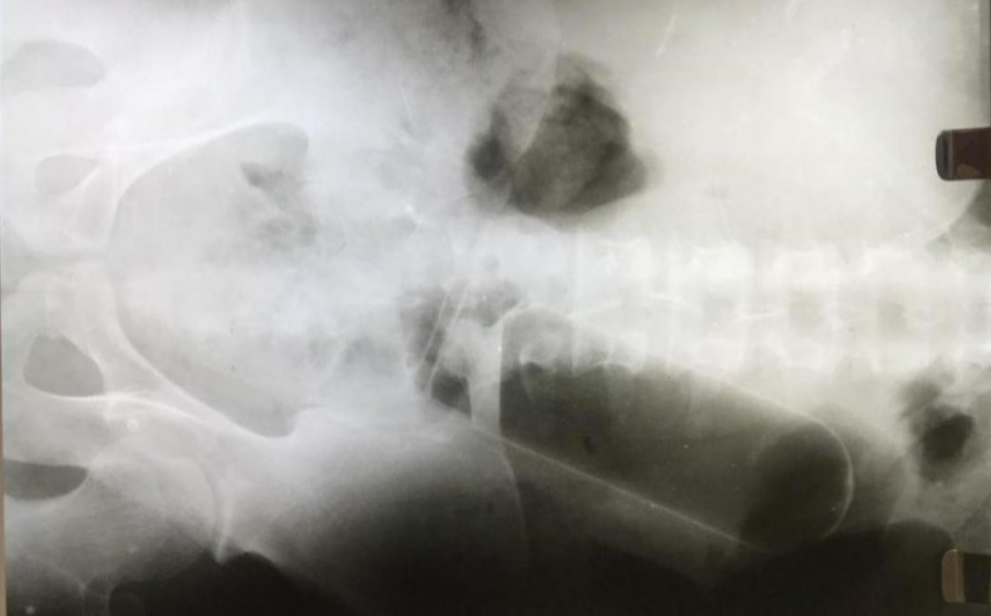

Após atendimento na recepção e passar por triagem, o médico pediu que fosse feito um exame de Raio X, e após feito, foi verificado que no estômago do paciente havia uma garrafa do tipo térmica, confeccionada em alumínio. Segundo a namorada, ela mesma teria introduzido o objeto no ânus do namorado a pedido dele.

Devido a profundidade em que estava inserido o objeto, e por não ter como alcançar para retirar em um procedimento simples, os médicos do hospital encaminharam o paciente para o Hospital Municipal de Ji-Paraná, onde o mesmo seria submetido a uma cirurgia para retirada da garrafa.